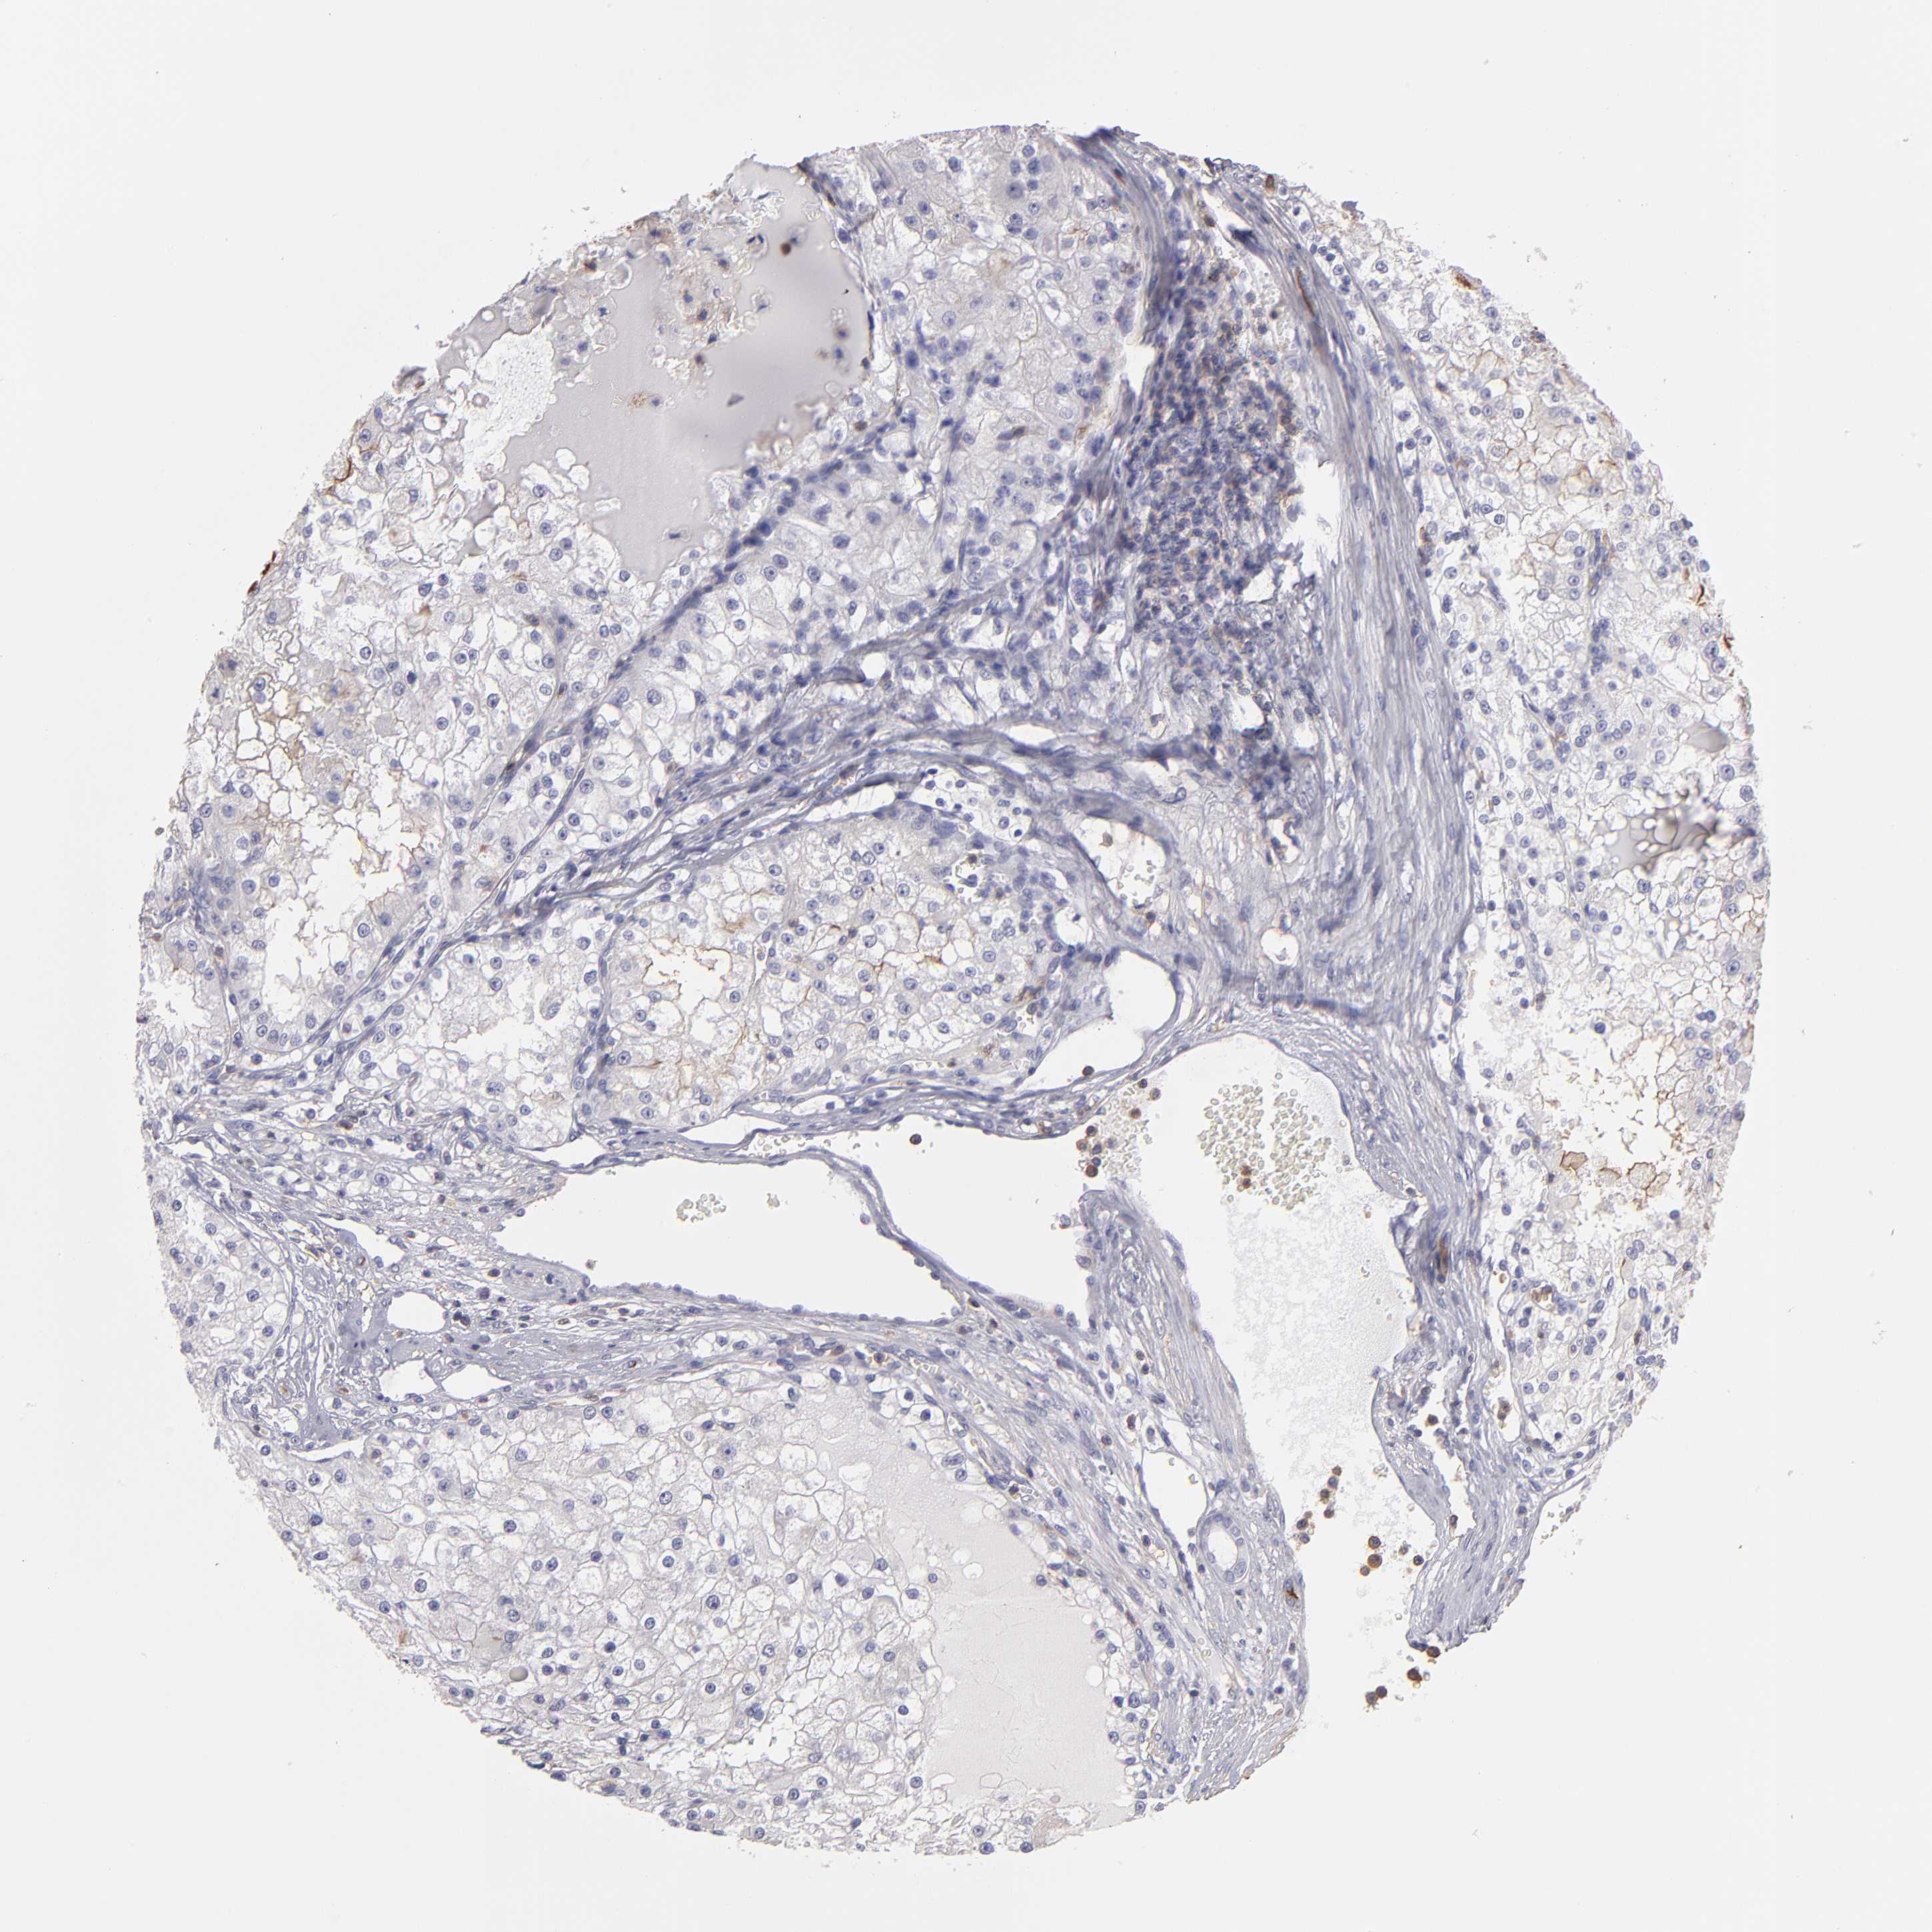

KIDNEY RENAL CLEAR CELL CARCINOMA (TCGA) - Interactive survival scatter ploti

The Survival Scatter plot shows the clinical status (i.e. dead or alive) for all individuals in the patient cohort, based on the same data that underlies the corresponding Kaplan-Meier plots. Patients that are alive at last time for follow-up are shown in blue and patients who have died during the study are shown in red.

The x-axis shows the expression levels (FPKM) of the investigated gene in the tumor tissue at the time of diagnosis. The y-axis shows the follow-up time after diagnosis (years). Both axes are complimented with kernel density curves demonstrating the data density over the axes. The top density plot shows the expression levels (FPKM) distribution among dead (red) and alive patients (blue). The right density plot shows the data density of the survived years of dead patients with high and low expression levels respectively, stratified using the cutoff indicated by the vertical dashed line through the Survival Scatter plot. This cutoff is automatically defined based on the FPKM cutoff that minimizes the p-score. The cutoff can be changed by dragging the vertical line or by entering a cutoff value in the square labeled "Current cut-off".

Under the Survival Scatter plot the p-score landscape (black curve; left axis) is shown together with dead median separation (red curve; right axis). Dead median separation is the difference in median mRNA expression between patients who have died with high and low expression, respectively. It is calculated as follows: median FPKM expression of dead patients with high expression - median FPKM expression of dead patients with low expression. This is intended to aid the user in visually exploring custom cutoffs and the associated p-scores and dead median separation.

Individual patient data is displayed and can be filtered by clicking on one or more of the category buttons on the top of the page. Categories describing expression level and patient information include: high, low, alive, dead, female, male and tumor stages. The scale of the x-axis can be toggled between linear and log-scale by clicking on the "x log" button. Mouse-over function shows TCGA ID, patient information and mRNA expression (FPKM) for each patient.

& Survival analysisi

Kaplan-Meier plots summarize results from analysis of correlation between mRNA expression level and patient survival. Patients were divided based on level of expression into one of the two groups "low" (under cut off) or "high" (over cut off). X-axis shows time for survival (years) and y-axis shows the probability of survival, where 1.0 corresponds to 100 percent.

ABCB1 is potential prognostic, high expression is favorable in Kidney Renal Clear Cell Carcinoma (TCGA)

Best expression cut offi

Based on the FPKM value of each gene, patients were classified into two groups and association between prognosis (survival) and gene expression (FPKM) was examined. The best expression cut-off refers the FPKM value that yields maximal difference with regard to survival between the two groups at the lowest log-rank P-value. Best expression cut-off was selected based on survival analysis .

When clicking on this number, the vertical dashed line indicating cut-off, the interactive survival plot, and the Kaplan-Meier curve will be adjusted to show results based on the best expression cut-off.

: 4.93

Median expressioni

Median expression refers to the median FPKM value calculated based on the gene expression (FPKM) data from all patients in this dataset. When clicking on this number, the vertical dashed line indicating cut-off, the interactive survival plot, and the Kaplan-Meier curve will be adjusted to show results based on the median expression.

: N/A

Median follow up timei

Median follow up time refers to the median time (years) after diagnosis with this type of cancer, based on clinical data from all patients in this dataset.

P scorei

Log-rank P value for Kaplan-Meier plot showing results from analysis of correlation between mRNA expression level and patient survival.

N/A

5-year survival highi

5-year survival for patients with higher expression than the expression cutoff.

For melanoma and glioma, 3-year survival is shown.

5-year survival lowi

5-year survival for patients with lower expression than the expression cutoff.

Average pTPM 9.6

Number of samples 521